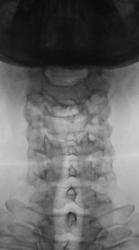

На рентгенограммах стато-функциональные изменения в шейном отделе выражены не отчетливо, можно описать как патологию, но можно описать и как норму, а вот увеличение ширины ключично-акромиального сочленения есть, возможно имеет место быть старый разрыв связок ключично-акромиального сочленения.